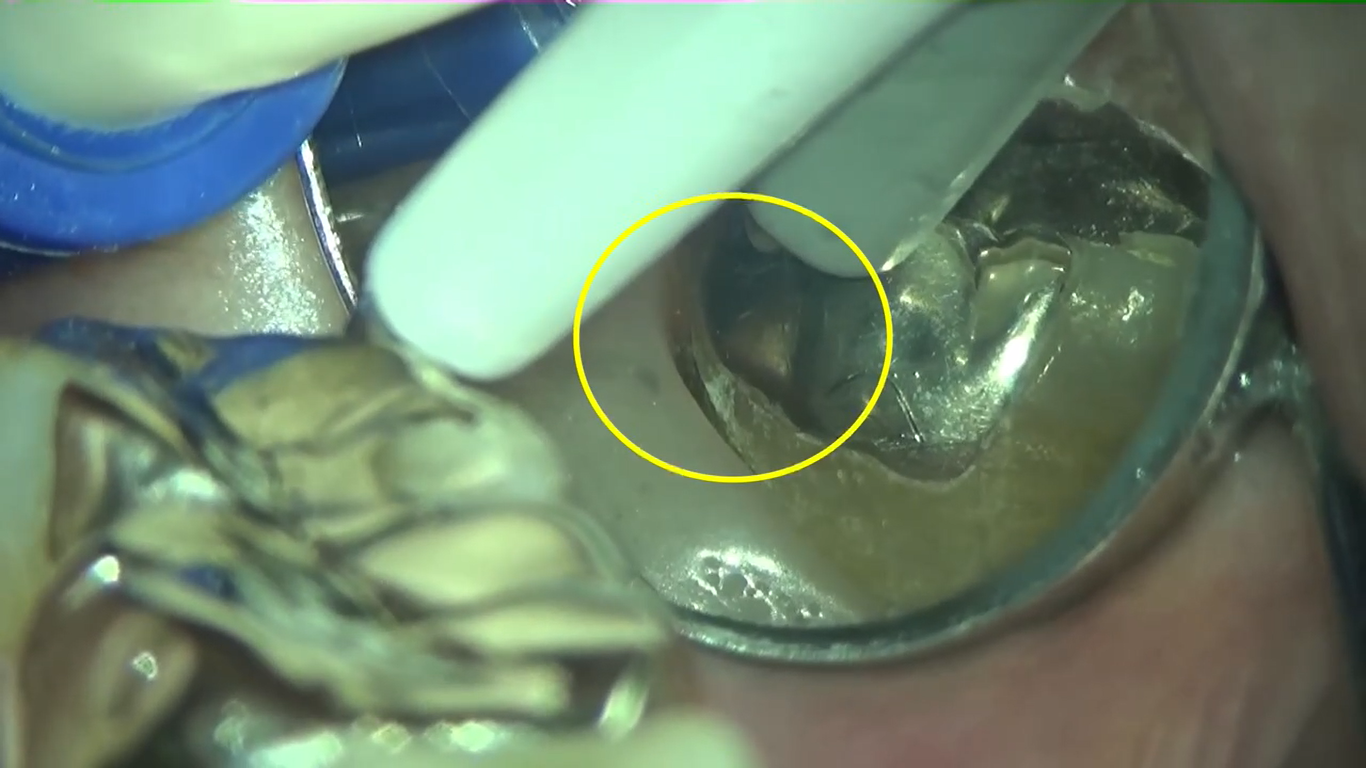

かくれ歯石

こんにちは! 南館歯科クリニックの歯科衛生士 山崎です。 マイクロスコープを使って歯周病治療を行っている映像です。 https://youtu.be/zOXy3y23Gj0 右上1番奥の歯の後ろ側に、…